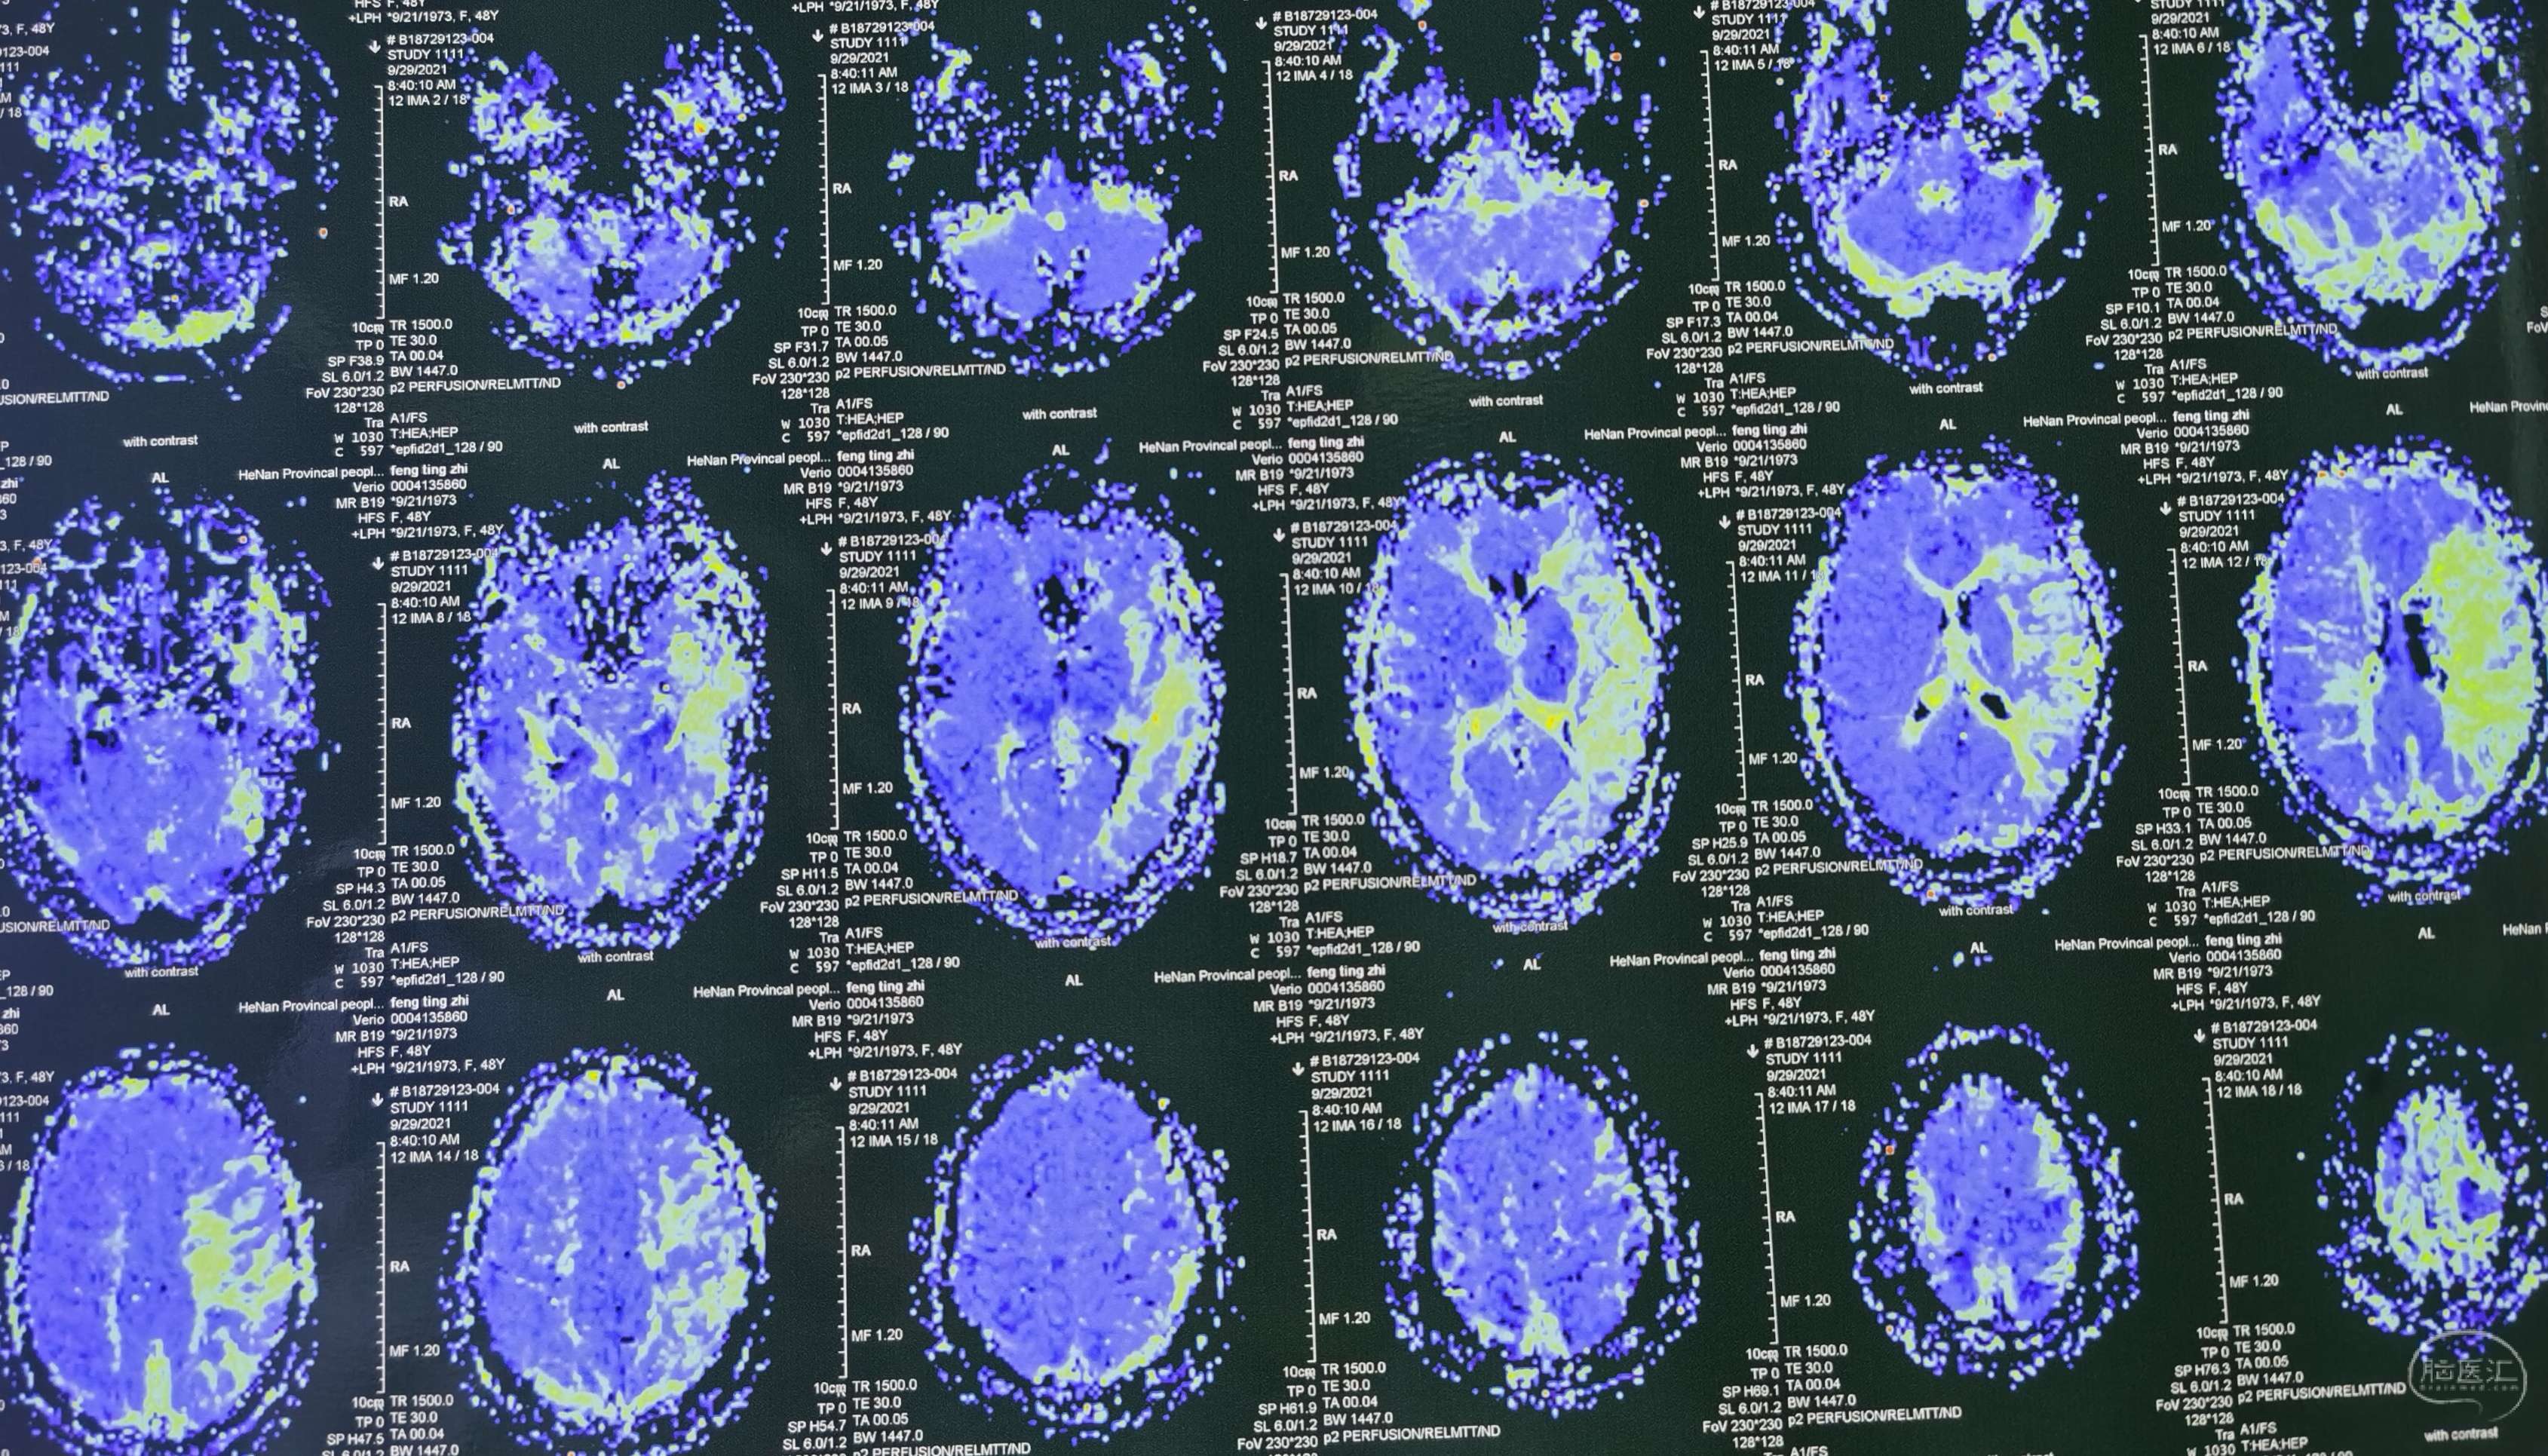

磁共振灌注提示:左侧大脑半球低灌注改变。

磁共振灌注提示:双侧大脑半球低灌注改变。